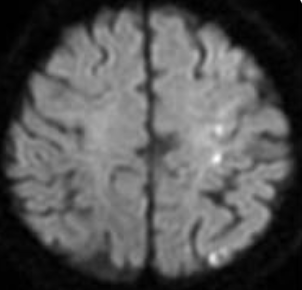

高性能オープンMRI / 当日検査・診断

磁力を使って、脳、脊髄だけでなく骨や血管の撮影ができるオープンMRIを導入。開放的でストレスなくリラックスをした状態での検査が可能です。また当院では、MRI検査だけでなく、血液検査も当日検査、当日結果説明をすることができます。